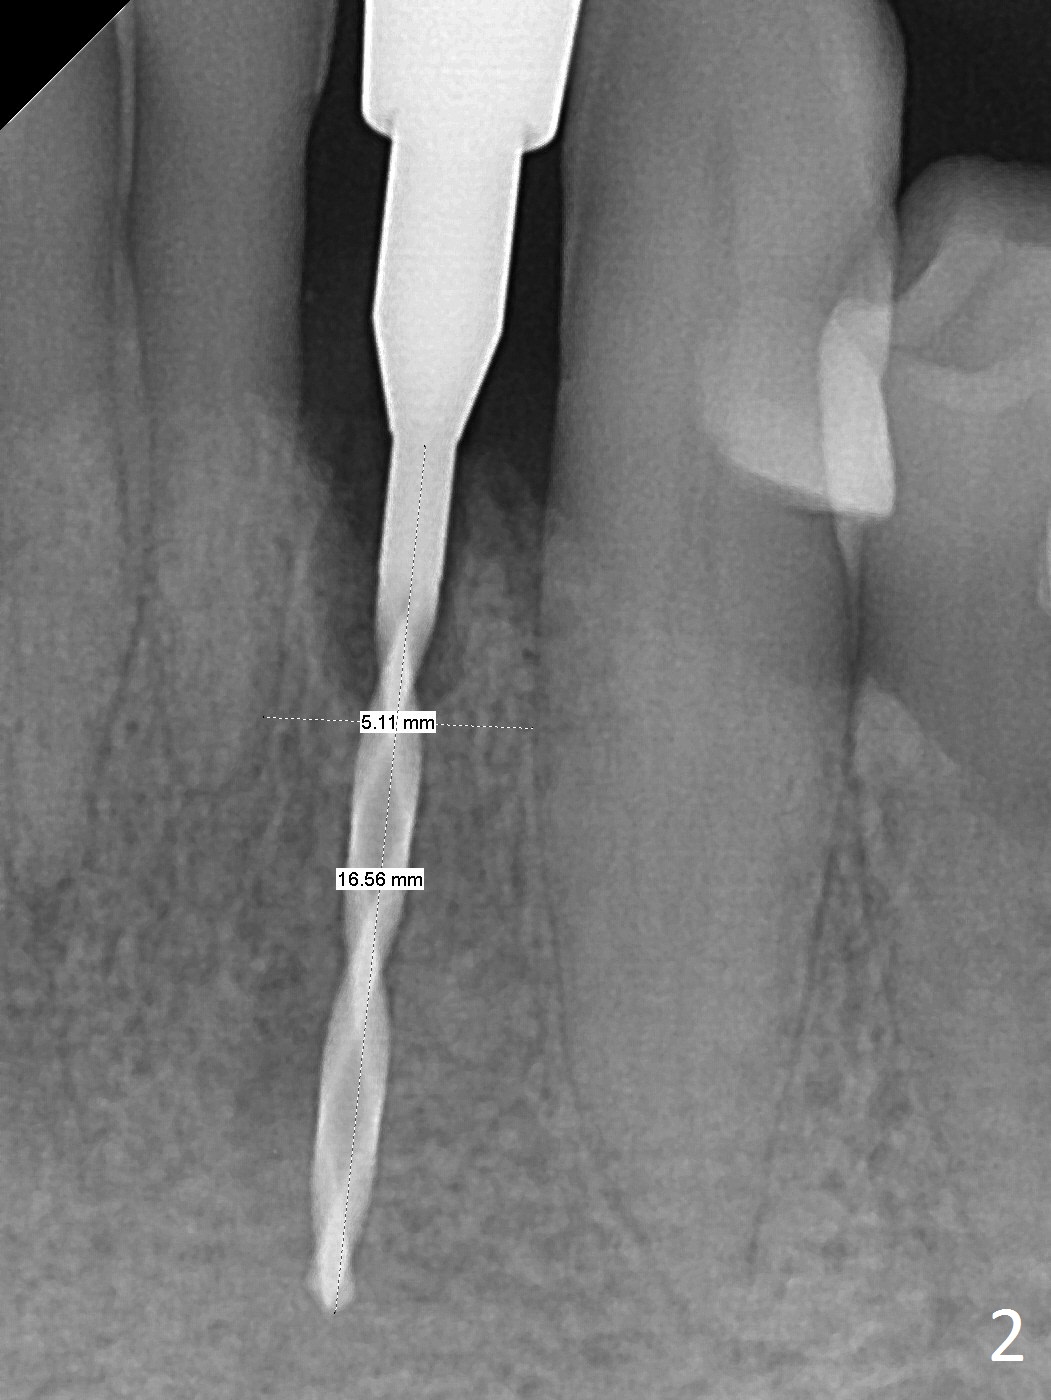

The tooth #23 is going to be extracted because the patient cannot masticate normally with mobility (Fit.1). The gingival depth is measured 2-4 mm after extraction. The 1st intraop PA taken with 1.2 mm drill for 16 mm shows the mesiodistal width is 5.11 mm (Fig.2); a 2.5x14(2) mm 1-piece implant is placed with >35 Ncm (Fig.3 with allograft placed). Following abutment preparation, an immediate provisional is fabricated to close the socket (Fig.4 P). There is no bone loss (Fig.5) or gingival inflammation (Fig.6 after reprep) 3 months postop. The narrow implant (2.5 or 2.0 mm) is indicated in the narrow edentulous space. The distal crest seems to be reduced in density and lower in height 1 year 7 months (Fig.7) and 1 year 11 months (Fig.8) post cementation. The severity does not worsen probably related to use of water pik. The crown looks bulky probably due to too large the abutment and too buccal placement of the implant (Fig.9, 10, as compared to Fig.1). A 2 mm implant may help?